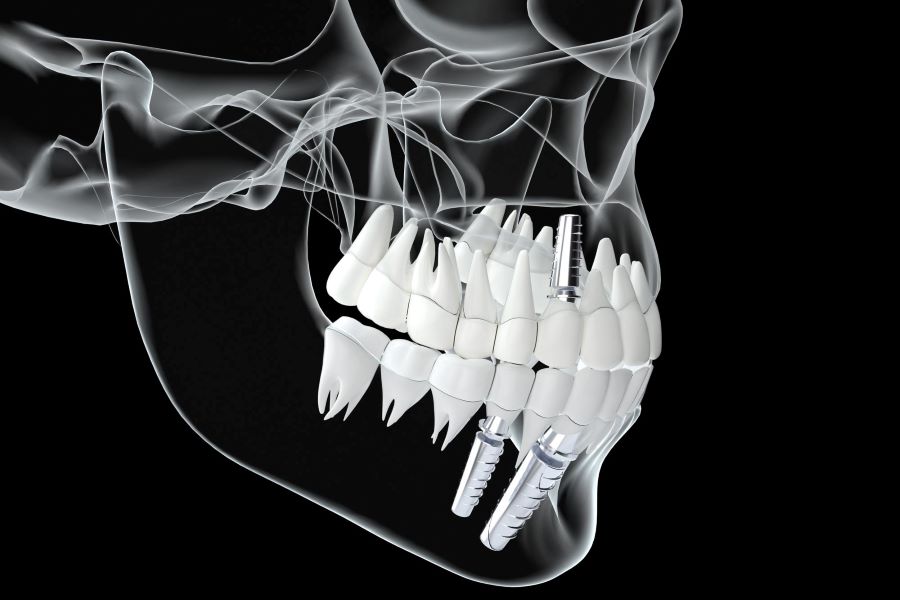

ایمپلنتها در دنیای پزشکی نقش بسیار مهمی دارند. اگر جوش خوردن ایمپلنت به شکل صحیح انجام بگیرد، میتوانید بدون هیچ نگرانی خاصی برای مدتهای مدیدی از آن استفاده کنید؛ اما جوش نخوردن ایمپلنت به شکل کامل مشکلات مختلفی را برای افراد ایجاد میکند.

جوش خوردن را میتوان اصلیترین مرحله پس از کاشت ایمپلنت دانست. در این روند ایمپلنت با فک شما اتصال مناسبی برقرار میکند و ساختاری ویژه بین این دو قطعه ایجاد میشود. این پیوند منجر به استحکام بیشتر ایمپلنتهای شما خواهد شد.

ایمپلنت را میتوان در رده برترین راهکارهای موجود در حوزه دندانپزشکی قرار داد که هر ساله افراد بسیار زیادی از آن استفاده میکنند. ایمپلنتها باید به طور کامل با فک شما جوش بخورند تا بتوانید بدون مشکل خاصی به فعالیتهای روزمره خود ادامه دهید.